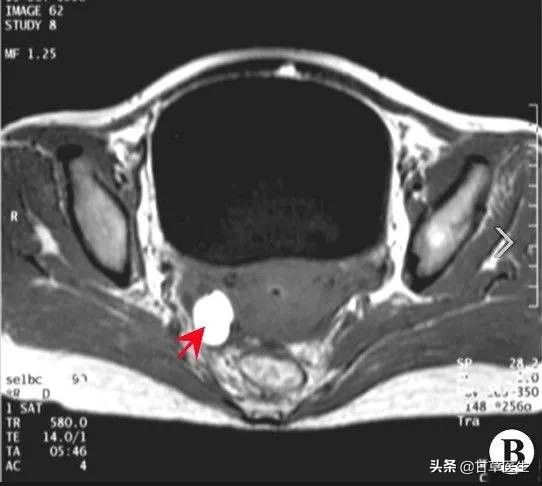

软巢囊肿示意图